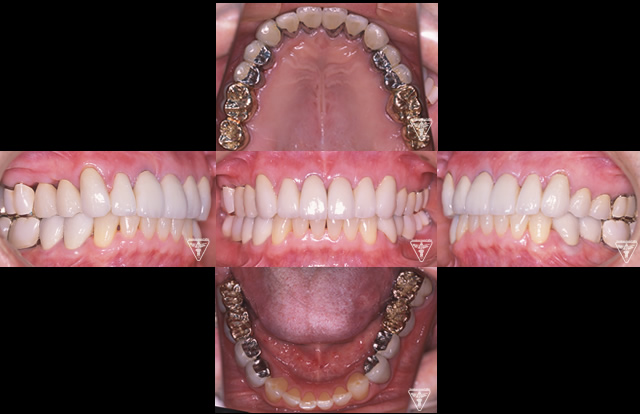

SHILLA・Systemによる咬合平面・歯列弓の設定

治療前後の比較

治療前

治療後

治療前

治療後